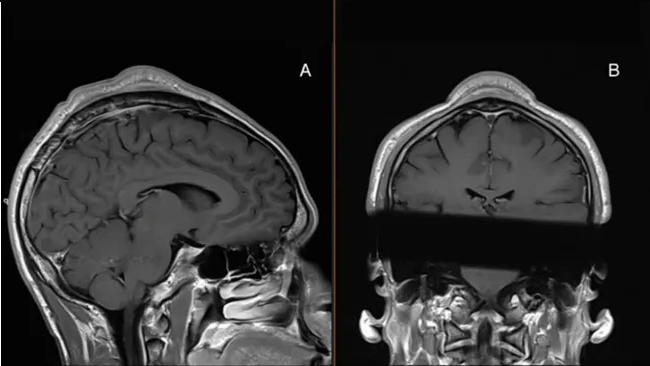

После осмотра болезненной выпуклости и проведения структурного сканирования черепа пациента врачи определили, что между кожей и черепом находится мягкая масса, но также и то, что кожа над массой и кость под ней были значительно толще окружающих их тканей. Они решили хирургическим путем удалить массу, а также сбрить скальп мужчины до уровня окружающих тканей.

Фото: BMJ Case ReportsИзвестное как «синдром чрезмерного использования брейкдансера», это странное состояние, связанное с брейкдансом, было лишь изредка научно документировано, но, по-видимому, хорошо известно среди брейкдансеров, хотя его распространенность среди занимающихся до сих пор неизвестна. Немецкое исследование показало, что из 100 опрошенных брейкдансеров у 31% наблюдалась потеря волос, а у 24% появились безболезненные шишки на голове, а у 37 из них было воспаление кожи головы.